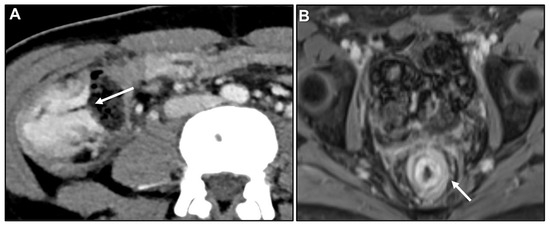

Peritoneal Carcinomatosis

- Burgain, C.; Germain, A.; Bastien, C.; Orry, X.; Choné, L.; Claudon, M.; Laurent, V. Computed tomography features of gastrointestinal linitis plastica: Spectrum of findings in early and delayed phase imaging. Abdom. Radiol. 2016, 41, 1370–1377. [Google Scholar] [CrossRef]

- Meyers, M.A. Intraperitoneal spread of malignancies and its effect on the bowel. Clin. Radiol. 1981, 32, 129–146. [Google Scholar] [CrossRef]

- DiPiro, P.J.; Tirumani, S.H.; Cruz, G.P.; Ramaiya, N.H.; Lester, S.C.; Shinagare, A.B. Lobular breast cancer: Patterns of intraabdominal metastatic spread on imaging and prognostic significance. Abdom. Radiol. 2019, 44, 362–369. [Google Scholar] [CrossRef]